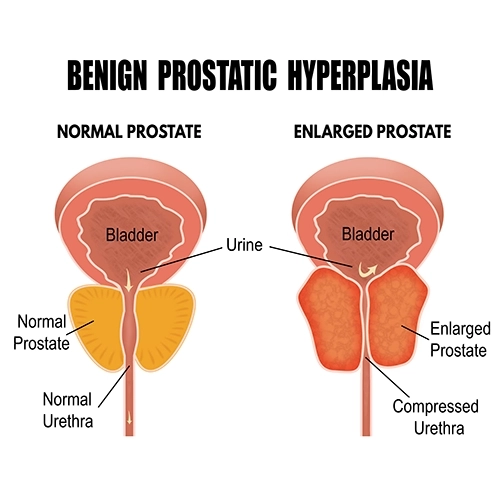

Millions of men over 50 will try to reduce their enlarged prostate this year, very few will succeed.

Studies show that, without the right strategies, men struggling to reduce their enlarged prostate systematically fail and resign themselves to a cycle of exhaustion and embarrassment.

Even though millions of men over 50 will try to reduce their enlarged prostate this year, very few will succeed.

It harbors natural compounds derived from plants that could potentially address BPH (benign prostatic hyperplasia). Scientists believe that saw palmetto might influence testosterone levels in the body and potentially diminish the activity of an enzyme responsible for fostering the proliferation of prostate cells.

Pygeum africanum extract+Pygeum comprises compounds that aid in reducing an enlarged prostate in males. This has the potential to alleviate urinary issues like weak urine flow and nocturnal urination.

Oral consumption of pygeum has shown efficacy in diminishing symptoms associated with BPH, such as reduced urine flow and incomplete bladder emptying during urination.

Pumpkin Seed Extract (seed)+The natural compounds found in pumpkin seeds have the potential to mitigate the impact of dihydrotestosterone on the prostate. Moreover, these compounds might impede the conversion of testosterone into dihydrotestosterone.

Pumpkin seeds encompass phytosterol, a protective compound believed to contribute to the reduction of prostate enlargement.

They have the potential to alleviate symptoms associated with BPH (benign prostatic hyperplasia). -

Eliminate The Constant Urge To Urinate:

Generates an anti-inflammatory effect on the prostate which puts less pressure on the urethra...

... Improves low urine flow and helps to fully empty the bladder.

Prostate Size Reduction:

Your prostate should be more the size of a walnut, not a lemon...

...Prosta-7 contains nutrients that help shrink the prostate in men with enlarged prostates...

...Contains phytosterol, which is a protective compound that may be responsible for reducing prostate enlargement.